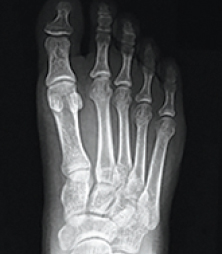

Instead of cutting the bone in half and shifting the top part over, the patented Lapiplasty® Procedure uses specially-designed instrumentation to rotate the entire deviated bone back into its normal anatomical position, naturally straightening your toe; removing the "bump" and associated pain. Innovative titanium plating technology5,6 permanently secures the unstable foundation, the root of your bunion problem. Most patients are able to walk within days of surgery.1 No cast is required; allowing patients to get back to the shoe wear of their choice and activities quickly.1

The patented titanium plating technology used with the Lapiplasty® Procedure enables patients to bear weight on their foot early.1 The ability to do so can dramatically improve your recovery process, allowing you to walk up to 6-8 weeks earlier than with the more traditional Lapidus approach (which was previously the only option for addressing the unstable joint).

Being able to walk in a surgical boot, as opposed to being completely non-weight bearing (in a cast with scooter or crutches) for 6-8 weeks, means that you will be getting back to a better quality of life faster; may return to most occupations more quickly; and will be less inconvenienced by bunion surgery.8